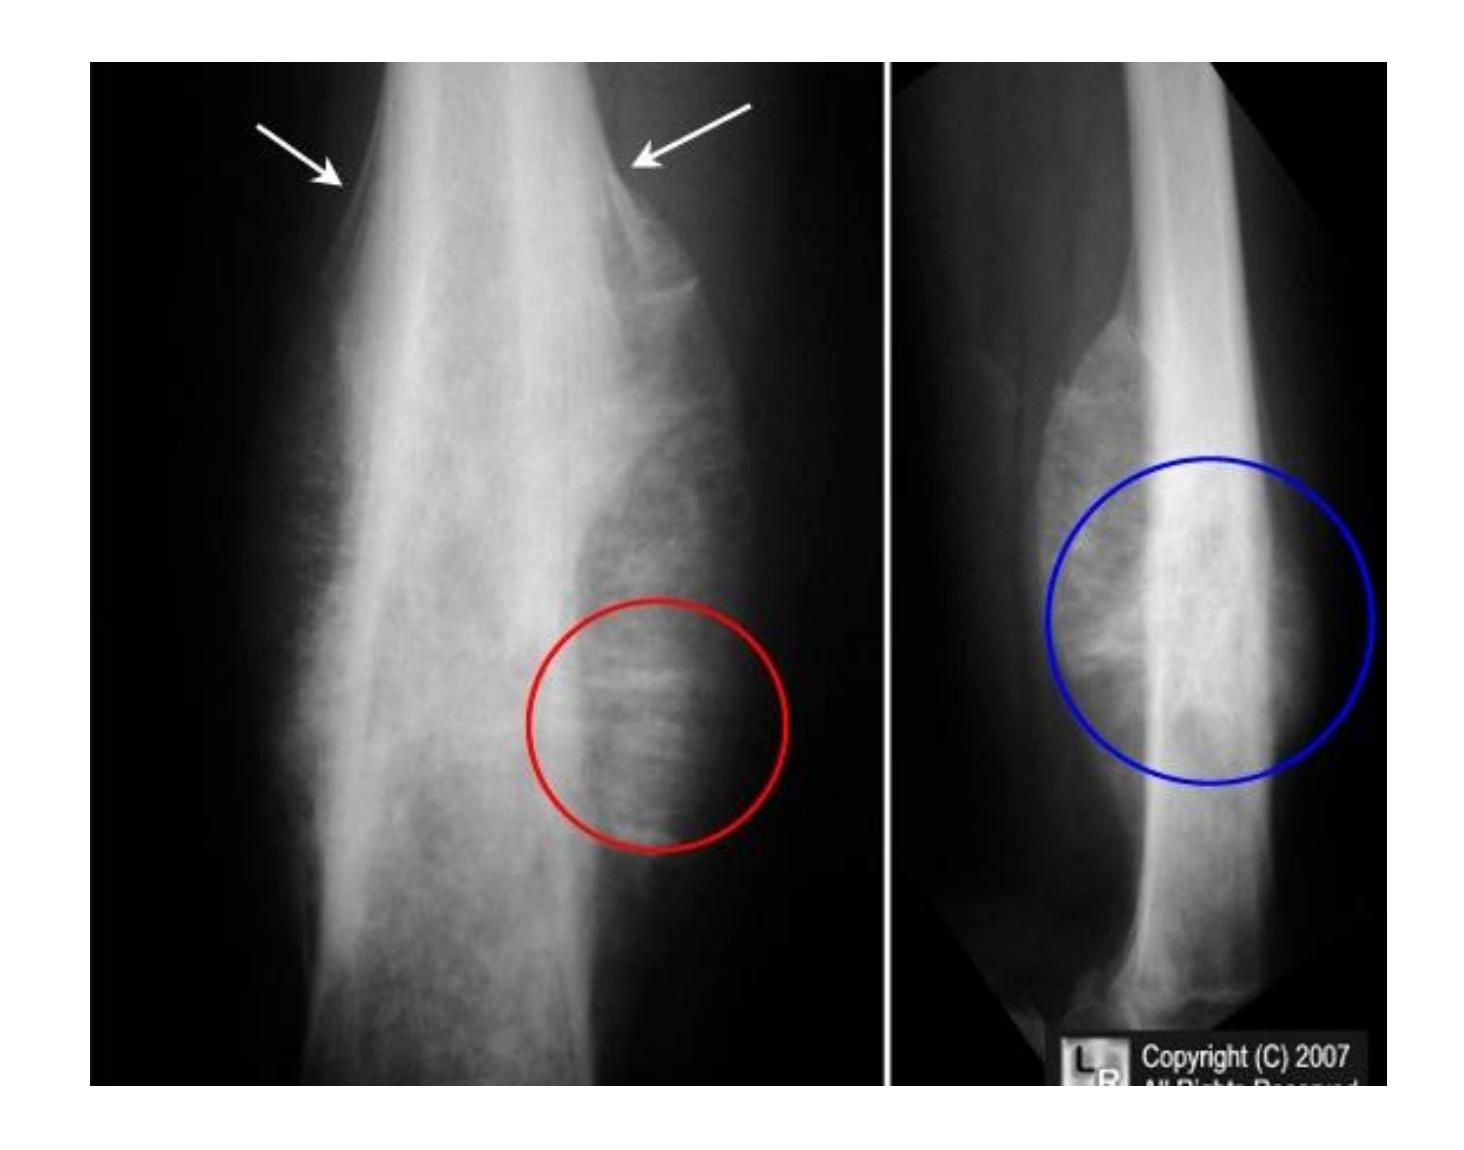

Which pattern of fractures is demonstrated in the attached X-ray?

- B. Segmental

Tibia and Fibula Fracture

Diagnosis: Segmental and comminuted fracture of tibia and fibula